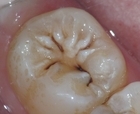

虫歯は、歯の表面にできる小さな穴や破損で、そこに細菌が感染することが原因で痛みを引き起こします。6歳ごろは、乳歯の根元が弱くなる時期であり、虫歯のリスクが高まります。虫歯を防ぐためには、正しい歯磨き習慣を身につけ、食後の口内ケアを行うことが重要です。

歯科医院では、歯の検査やレントゲン撮影が行われ、痛みの原因を特定します。その後、適切な治療法が提案されます。治療内容は、虫歯の治療や歯並びの調整、歯茎の炎症の治療などです。

歯科受診の際、まずはお子様の歯の状態を詳しく確認します。虫歯がないか、歯茎に炎症がないか、歯並びに問題がないかをチェックします。次に、レントゲン撮影を行い、目に見えない歯の問題がないかを確認することもあります。その後、必要に応じて治療を行います。例えば、虫歯が見つかった場合にはその治療、歯茎の炎症があれば抗炎症剤を使用した治療を行います。